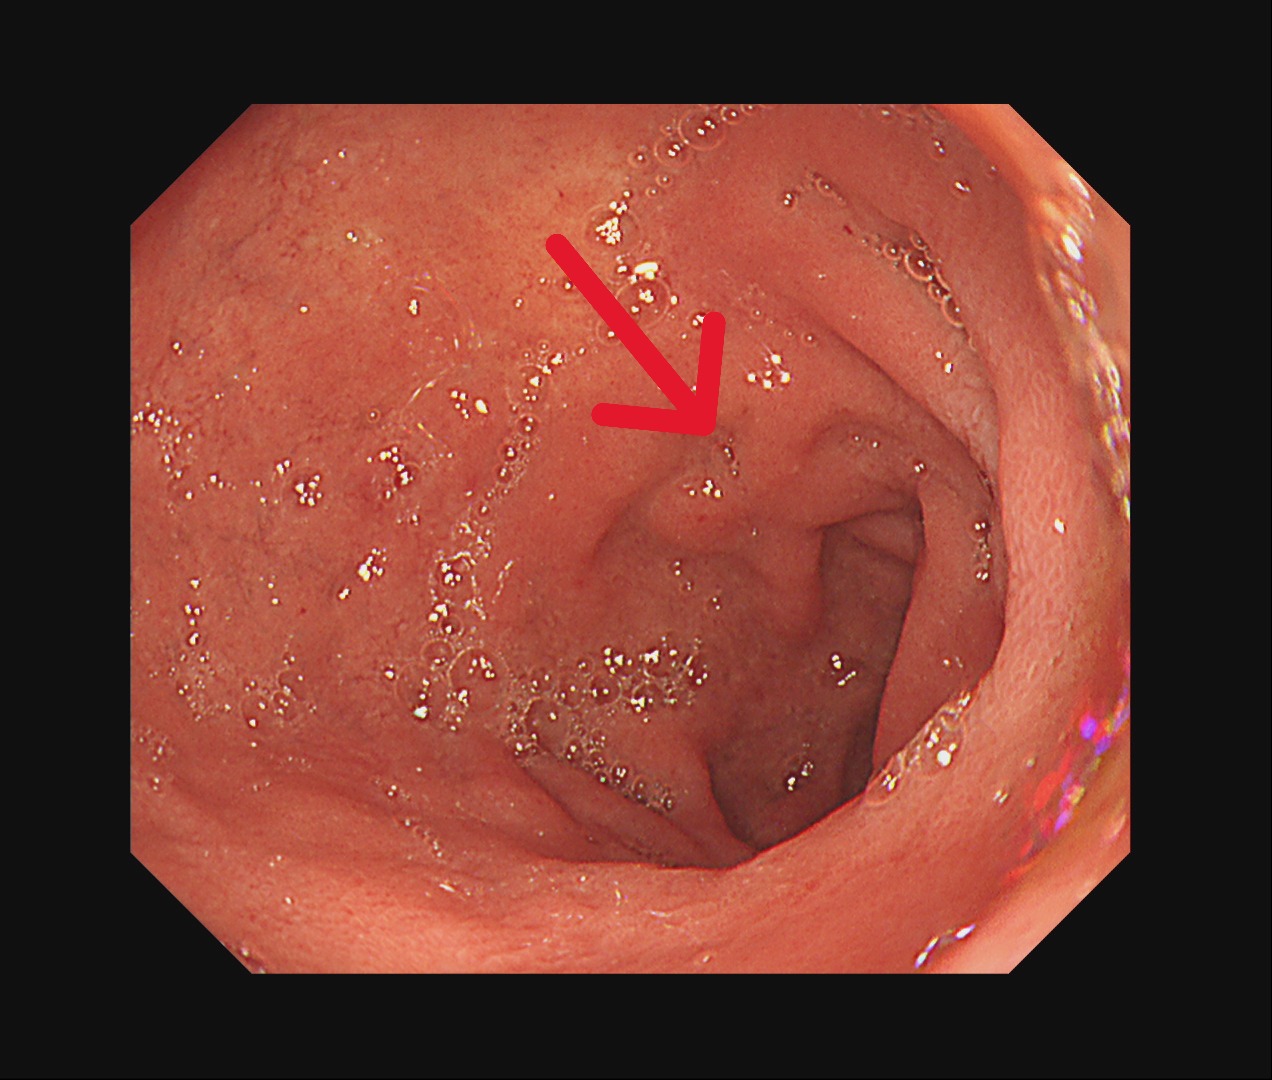

在為期兩個月的術前免疫治療合併化療期間,病人雖出現噁心、掉髮、倦怠等副作用,但家人每日陪伴、鼓勵,使他能堅定完成療程。隨著治療進展,患者症狀逐漸改善,胃痛減緩、進食量增加、精神與體力明顯好轉,全家人的心情也從陰霾中逐步走出。 腹部斷層掃描(治療後)

腹部斷層掃描(治療後)